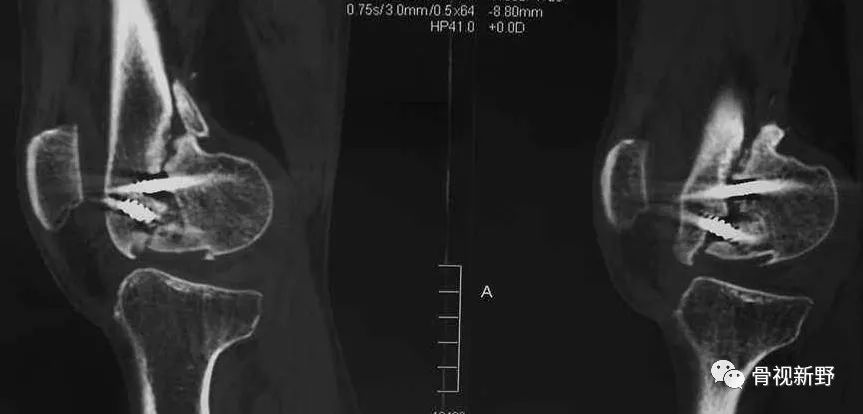

影像诊断:部分Hoffa骨折X线片不能提供明确的诊断,漏诊率较高。需要CT或MRI检查,并根据患者的病史、查体及影像学检查予以确诊。

部分Hoffa骨折普通X光片易漏诊

CT扫描在矢状位、轴位容易发现骨折及骨折线的走形方向

MRI不但可发现隐匿性骨折,还可发现合并的软组织损伤